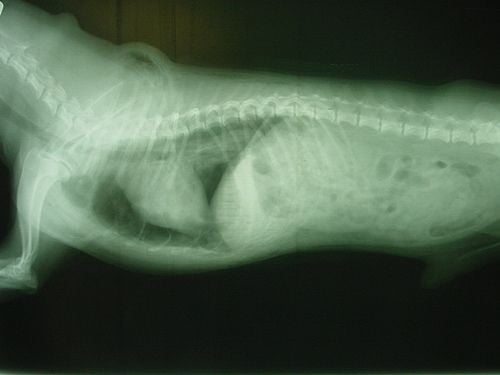

Miután a mellkasfal és a tüdő között csak egy vékony folyadékréteg található, ezért a tüdő a mellkas tágulásakor, a kialakuló „negatív” nyomás miatt, mindenkor követi a mellkas tágulását. A mellkasfal átható sérüléseikor azonban levegő kerül a mellkas fala és a tüdő közé, a mellkas tágulásakor kívülről levegő áramlik a mellüregbe, a tüdő nem tud kitágulni, összeesik. Az átható sérülés lehet harapás, lőtt seb, okozhatják bordatöréssel járó balesetek vagy vadászbalesetek (vaddisznóagyar vagy szarvasagancs) is. Közlekedési balesetek vagy nagy magasságból történt lezuhanás következtében megrepedhet a tüdő és a hörgők. Ilyenkor tehát a tüdőn keresztül kerül levegő a tüdő és a mellkasfal közé. A tüdőlebenyek összeesnek, a légmell (pneumothorax) kialakulása miatt lehetetlenné válik a légzés. A két tüdőfél között található a gátőr, mely a mellüreget két félre osztja. A gátőr (mediastinum) a szegycsonttól a gerinccsigolyák testéig húzódik, benne foglal helyet a szív és a nagy vérerek, a légcső. A nyelőcső mellett számos létfontosságú ideget is magában foglal. A középen kettéosztott mellüreg ily módon gyakorlatilag két, egymástól elszigetelt üregből áll. Egyoldali sérülések esetén ezért mindig csak az egyik tüdőfélnek megfelelően alakul ki légmell, vagyis csak az egyik tüdőfél esik össze. A légmell következtében kialakuló légszomj súlyossága a mellüregbe került levegő mennyiségétől függ. A légmellet a mellkas kopogtatásos vizsgálatával és röntgenfelvétel készítésével lehet diagnosztizálni. Azonnali életmentő beavatkozásként haladéktalanul le kell zárni a mellkas- sebet, elsősegélyként kötszer és műanyag fólia is megteszi, majd minél hamarabb sebészileg is össze kell zárni a sebszéleket. Belső sérülések, hörgőrepedés esetén ez természetesen nem lehetséges. Ilyen esetekben teljes nyugalomba kell helyezni a kutyát; egy nap elteltével túl lesz az életveszélyen és rövid időn belül a seb záródik és begyógyul. Mindkét tüdőfél sérülésekor oxigén lélegeztetésével – maszkon át vagy sátorban – igyekszünk fenntartani a gázcserét.